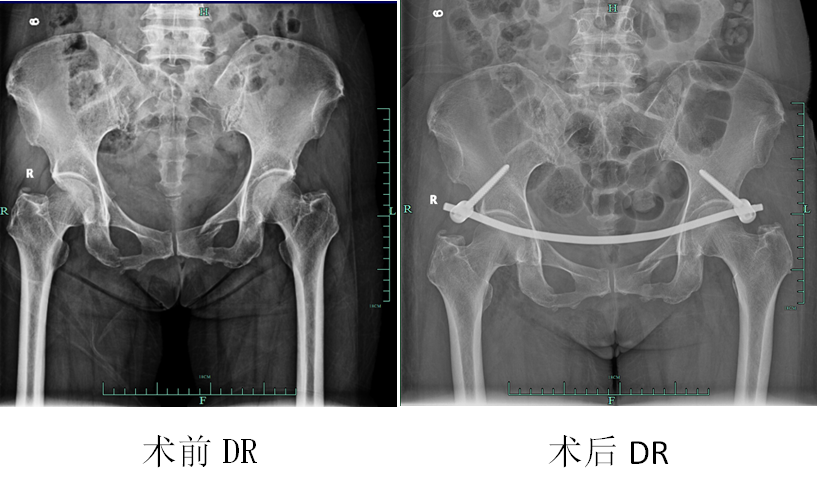

今年九月初,曾女士因腰部、骨盆部车祸外伤就诊于内江市中医医院创伤骨二科,经检查:

1.多发骨盆骨折(双侧耻骨上下支、右侧髂骨、右侧骶骨骨折);

2.右侧髋臼骨折;

3.腰椎横突骨折。患者系严重多发骨盆创伤,病情危重,骨盆内出血严重甚至危及生命。

故此,我院创伤骨二科主任高大新教授团队进行详细讨论和认真分析,决定采用最新微创Infix架内固定技术,对骨折进行闭合复位、皮内置钉架固定。经过周密术前准备,9月10日,高大新教授团队以最短时间为病人进行了闭合复位,微创骨盆内固定(Infix架)治疗。

手术用时不到1小时,出血量不足50ml;术中无任何神经血管损伤。术后恢复良好,术后第二天即可坐起,病人及家属对治疗效果非常满意。